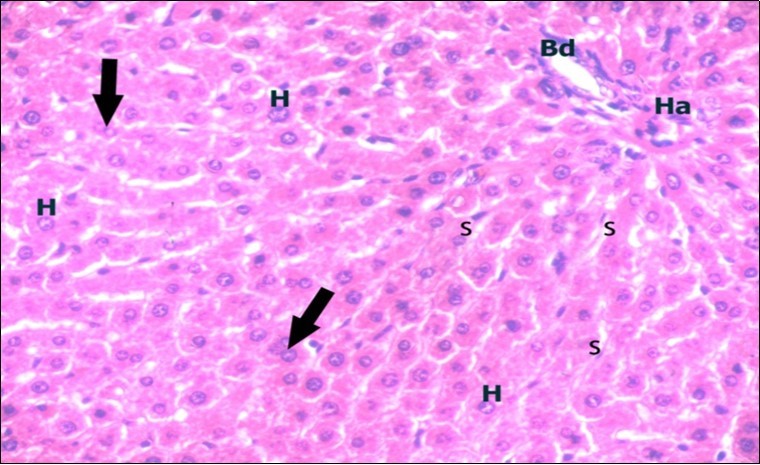

Examination of H&E stained sections of the 1st group (control group) revealed hepatic architecture of tightly packed cords of hepatocyte with vesicular nuclei and acidophilic cytoplasm radiating from the central vein (Figure 1). Portal area was composed of a portal vein, branch of hepatic artery and bile duct lined by single cuboidal cells with dark rounded nuclei. Blood sinusoids with their endothelial lining of Kuppfer cells were noticed in between hepatic cords (Figure 2). Examination of the liver sections of the 2nd group (vitamin E treated group) showed nearly the same histological features as the 1st group. The 3rd group (ZnONPs-treated group) showed a marked loss of the normal liver arrangement with dilated congested central veins and blood sinusoids. Most of hepatocytes had large cytoplasmic vacuoles and darkly stained nuclei other hepatocytes were ballooned (Figure 3). The portal area showed dilated congested portal vein with proliferation of bile duct, necrotic foci in between the hepatocytes with inflammatory cellular infiltration (Figure 4). The portal area showed also elongation of the endothelial lining of dilated congested portal vein and increasing amount of connective tissue fibers (Figure 5). There was congested hepatic artery with increasing thickness of its muscular layer (Figure 6). Bile duct showed proliferation with stratification of its epithelial lining (Figure 7).

Figure 2.A photomicrograph of a section in the liver of a control adult albino rat showing portal area containing bile duct (Bd) and hepatic artery (Ha). Polygonal hepatocytes (H) with rounded vesicular nuclei and acidophilic cytoplasm can be observed. Narrow radiating blood sinusoids (s) in between liver cords and their lining endothelium are seen. Binucleated cells are also seen (thick arrows). (H&E X400)